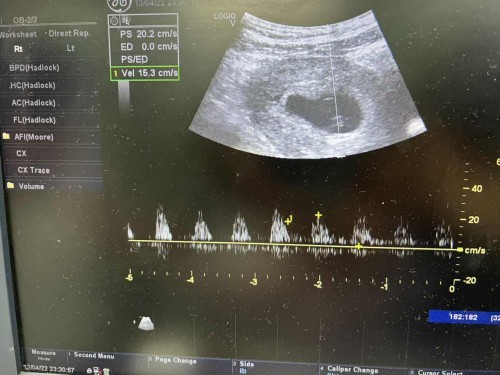

ขอโพสสอบถามแม่ๆค่ะ 1.รูปแรก ก่อนหน้านี้เราไปตรวจที่คลินิคมาวันที่ 26 มีค หมอบอกน้องหัวใจเต้นแล้ว แต่ยังตัวเล็กมาก เลยยังไม่ให้ฝากครรภ์ และนัดเราไปตรวจอีกทีวันที่ 12 เม.ย อายุครรภ์ได้ประมาณ 8w หมอบอกน้องไม่หายใจแล้ว นี่เสียใจมาก หมอบอกน้องไม่หายใจ เลือดไม่มีเข้าไปเลี้ยงตัวน้อง (ตรวจแบบทางช่องคลอด) รูปที่ 2 ห่างกันแค่วันเดียว วันที่ 13 เราลองไปตรวจที่ห้องฉุกเฉิน ที่ รพ. แต่เราไม่ได้แจ้งหมอนะว่าเราไปตรวจมาแล้วลูกไม่หายใจ เราไปเพราะอาการปวดท้อง คุณหมอเลยซาวน์ให้อีกที รอบนี้คุณหมอบอกน้องปกติดี น้องหายใจ ให้ดูคลื่นหัวใจน้อง แต่หมอบอกน้องตัวเล็กมาก เรานี่แอบดีใจ (ตรวจแบบซาวน์จากหน้าท้อง) ..แต่ทำไมที่คลินิคตรวจแบบนั้น ตอนนี้เรากังวลมาก ว่าสรุปน้องยังอยู่ไหม เครียดมาก วันที่ 16 นี้ว่าจะไป รพ ฝากครรภ์อีกที แม่ๆคนไหนเคยเจอแบบเราบ้างค่ะ